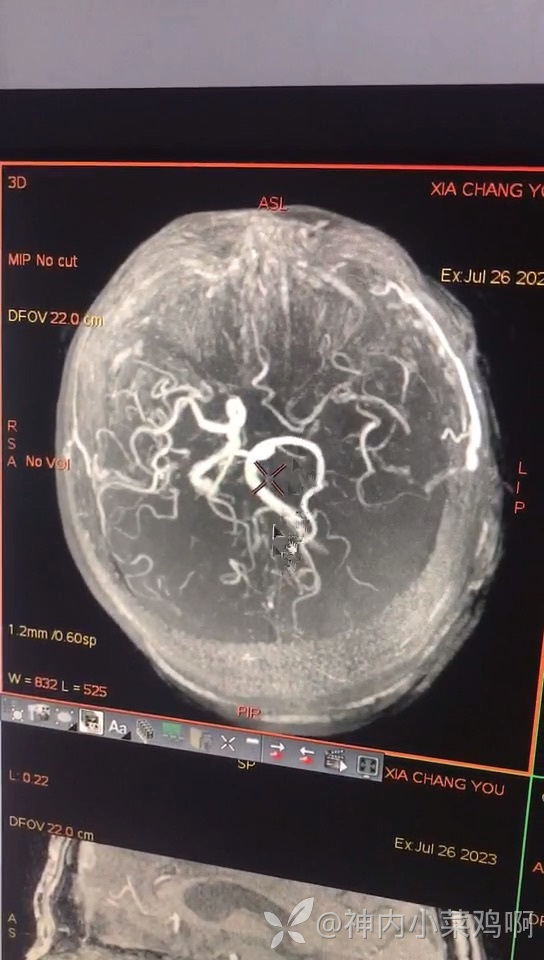

患者发病时间短,于急诊行阿替普酶静脉溶栓,溶栓后1小时患者肢体麻木消失。返回病房患者突发抽搐,表现为右上肢及右侧口角、颜面不自主抖动,无舌咬伤及尿便失禁,予地西泮10mg静脉推注症状未缓解;继之以250氯化钠溶液及60mg地西泮静点,患者抽搐症状逐渐控制。予依达拉奉右砍纯及优瑞克林、银杏二帖静点,予阿加曲班静脉泵入。第二日查看患者意识转清后,患者躁动,不能理解家人问话,执意起床,予地西泮静点及苯巴比妥肌肉注射,患者血压偏低90-100左右,排尿费力予导尿,进食不能予补液1000ml,第三日患者仍躁动,可理解问话,下胃管鼻饲饮食会抽见咖啡色胃内容物,予护胃保护胃黏膜,回抽无咖啡色胃内容物,粪便隐血阳性。完事头核磁及血管如下。现患者仍有躁动,执意起床,是否是病灶所致还是主观因素,患者影像病灶发病机制是否低灌注所致,患者前俩日进食不能,补液量1000左右,频繁镇静血压偏低。现能否给予抗板药物,是否该补液治疗,怎么补,补什么?求助各位大神!化验:血液无明显高凝、炎性指标轻度升高,离子正常、酮体阳性,高同型40+,高血脂。